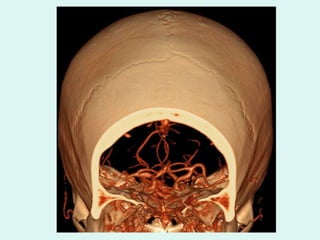

RECONSTRUÇÃO DE VOLUME

ANGIO CT INTRACRANIANA VERTEBRAIS

CEREBRAL MÉDIA ESQ. BASILAR VERTEBRAL ESQ . ANGIO CT INTRACRANIANA

ANGIO CT INTRACRANIANA BASILAR

ANGIO CT INTRACRANIANA BASILAR CEREBRAL POSTERIOR

ANGIO CT INTRACRANIANA CEREBRAL MÉDIA ESQ.